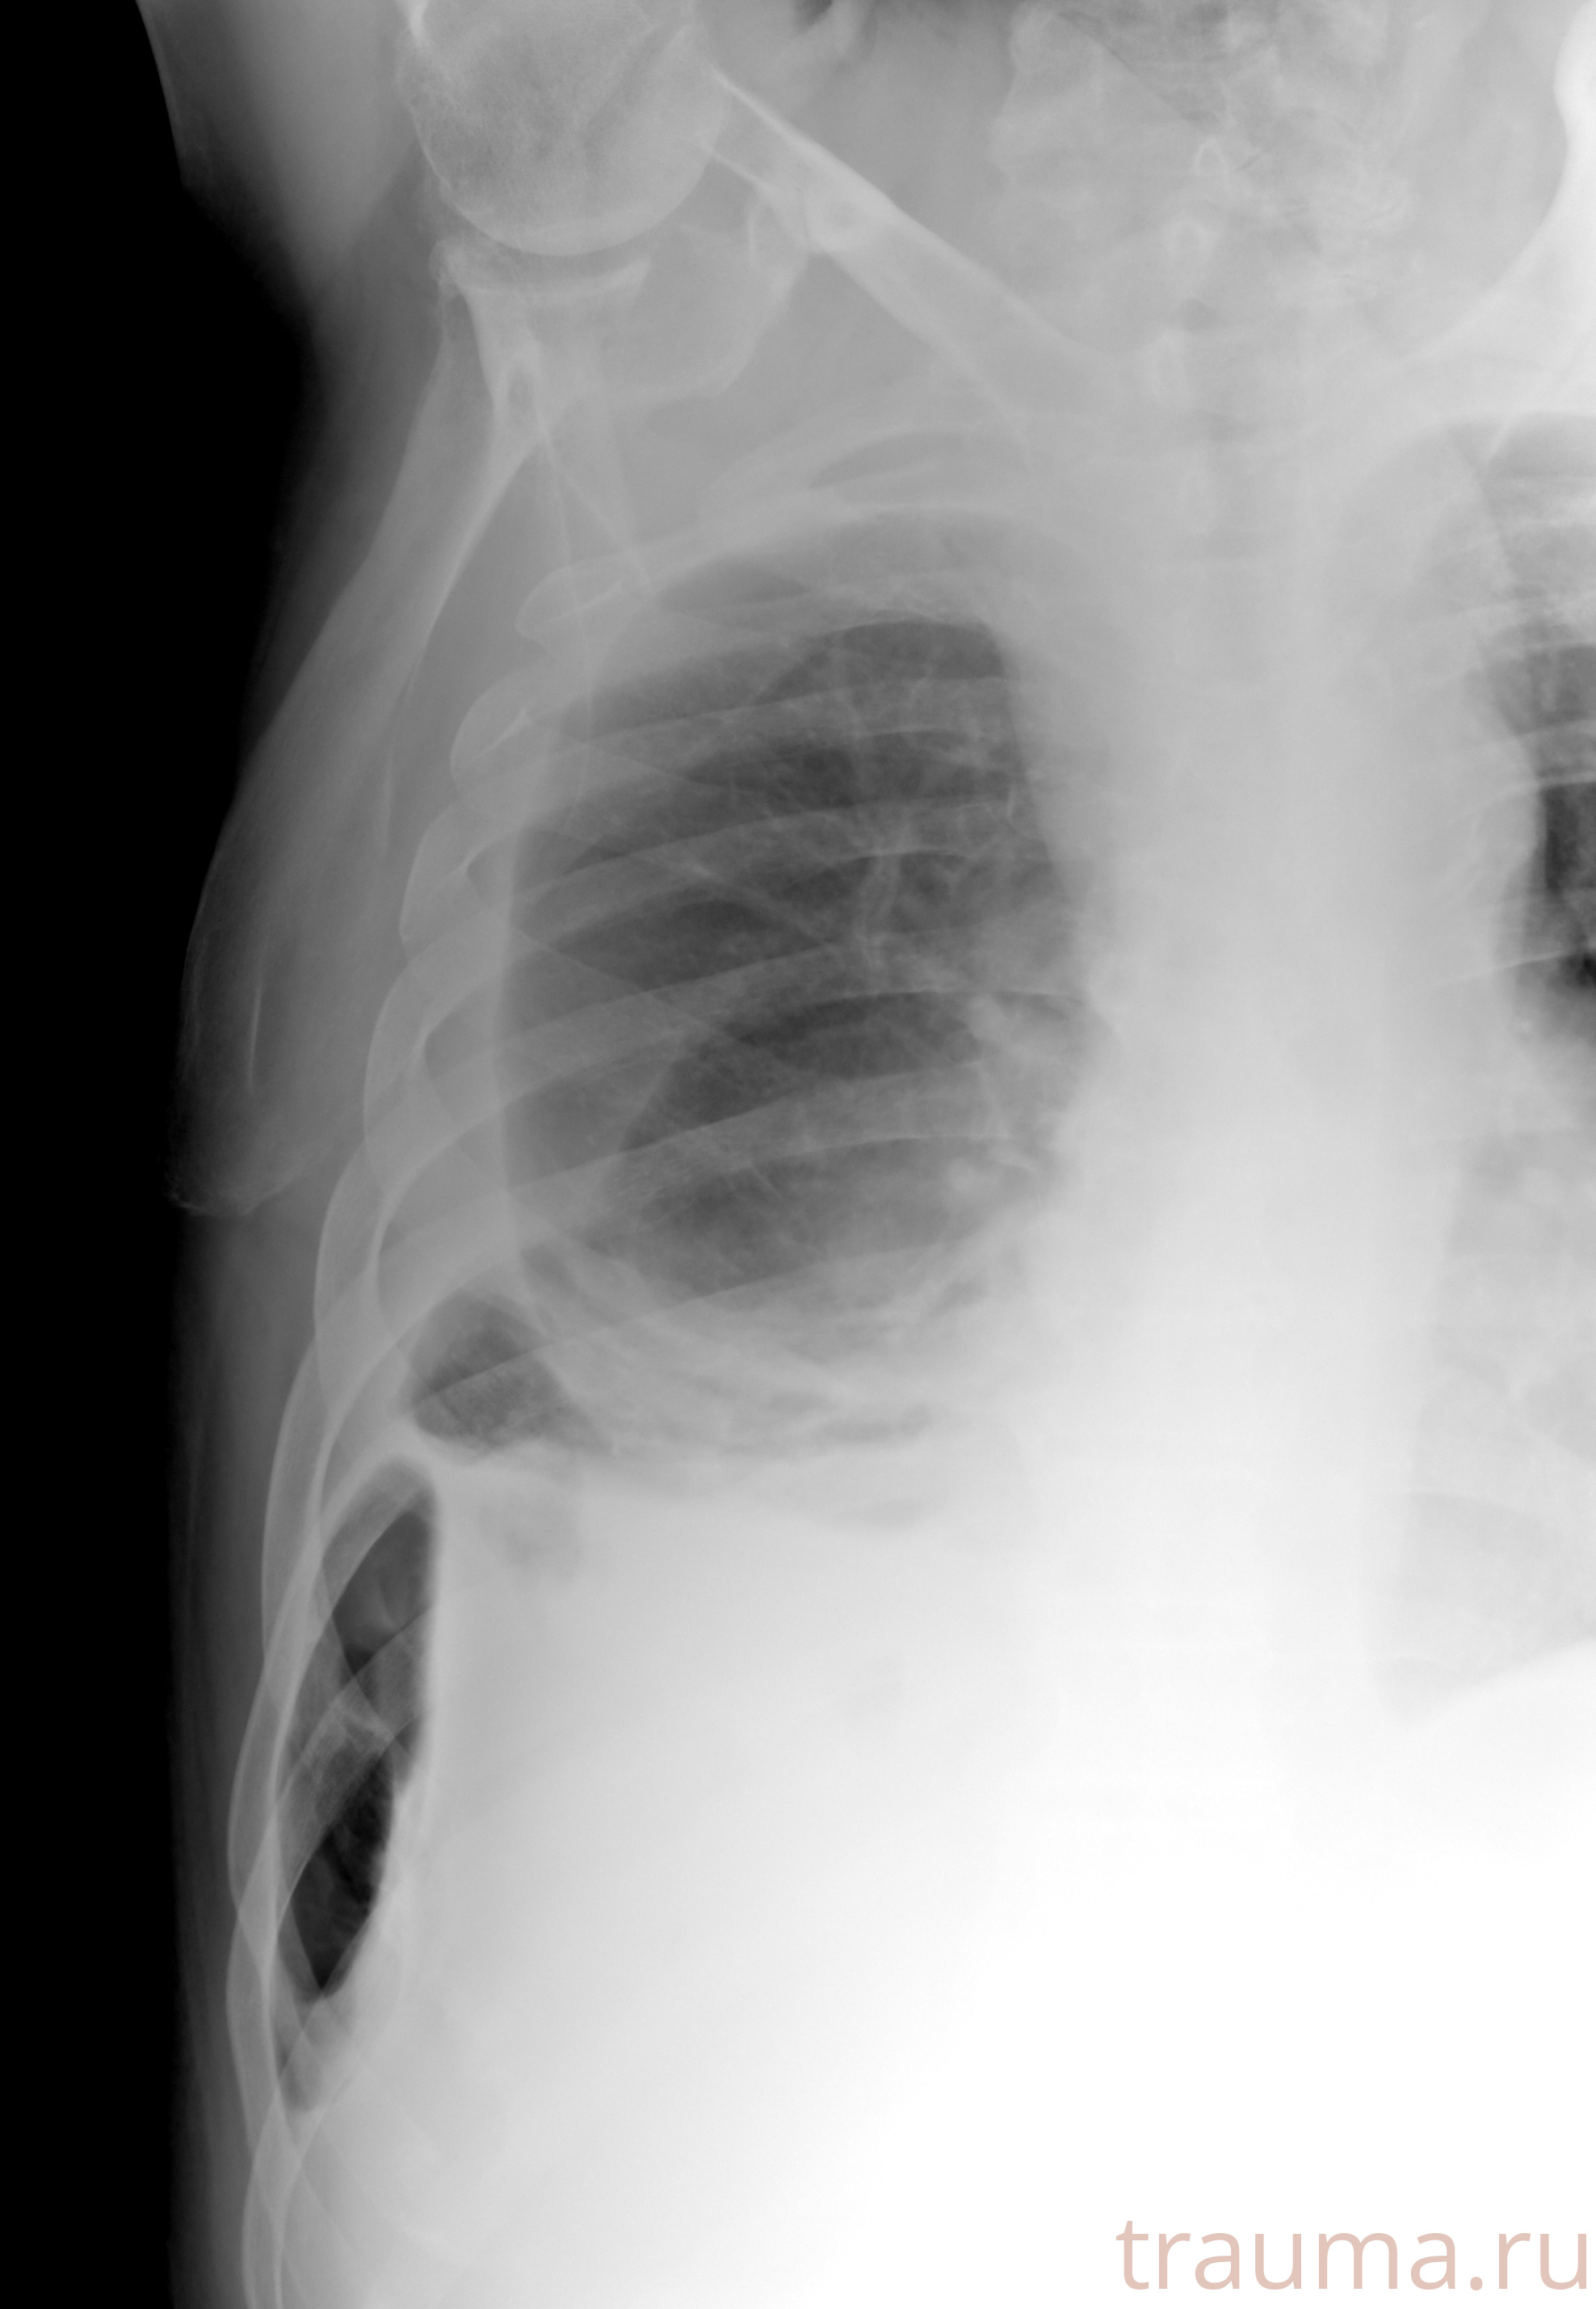

Рентгенограммы

Рентген на дому: по вашему адресу приезжает врач-рентгенолог, травматолог-ортопед с мобильным рентгеновским аппаратом, проводит диагностику травмы или заболевания, делает необходимые рентгенограммы, дает рекомендации по дальнейшему лечению. Получить качественные снимки в домашних условиях возможно благодаря уникальной методике, разработанной МосРентген Центром для института  Склифосовского

при переломе шейки бедра и пневмонии от компании МосРентген Центр - партнера Института имени Склифосовского